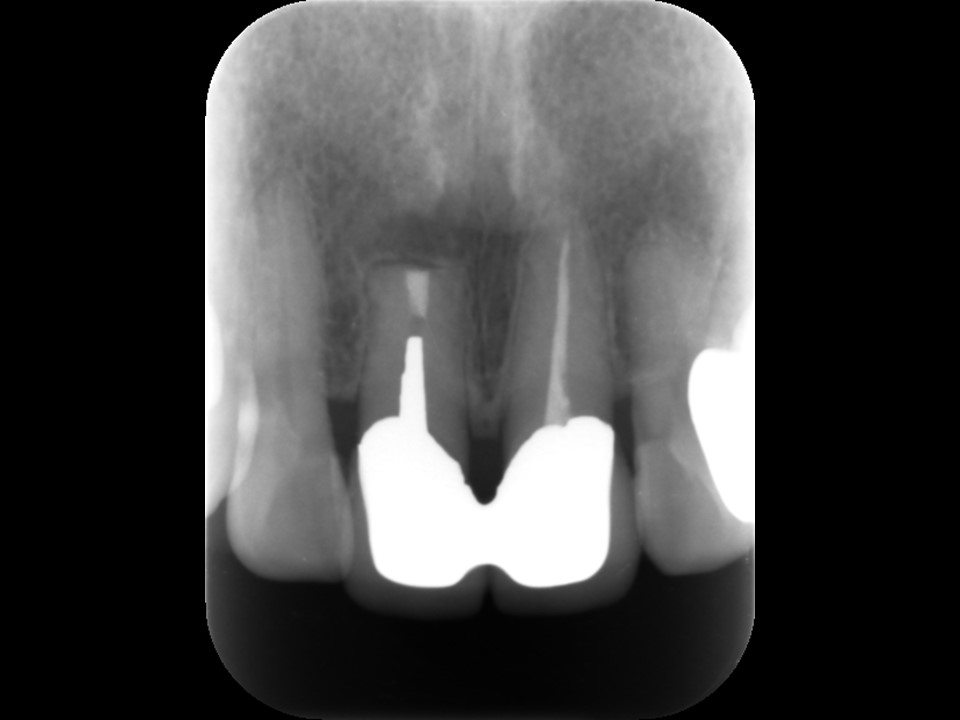

上顎前歯部は根管充填されているものの不十分で、歯根の先端には根尖病変と思われるX線透過像を認めます。以前の治療で根尖部はすでに壊れており、根尖外には破折したファイルが迷入しています(矢印)。外科的にファイルの撤去が必要なケースです。

術前レントゲンおよびCT画像です。上顎前歯に連結したセラミッククラウンが装着してありますが、根管充填は不十分です。

根尖部には根尖病変と思われる黒いX線透過像を認めます(矢印)。すでに一度歯根端切除が行われているため、隣在歯と比べて歯根が短くなっています。